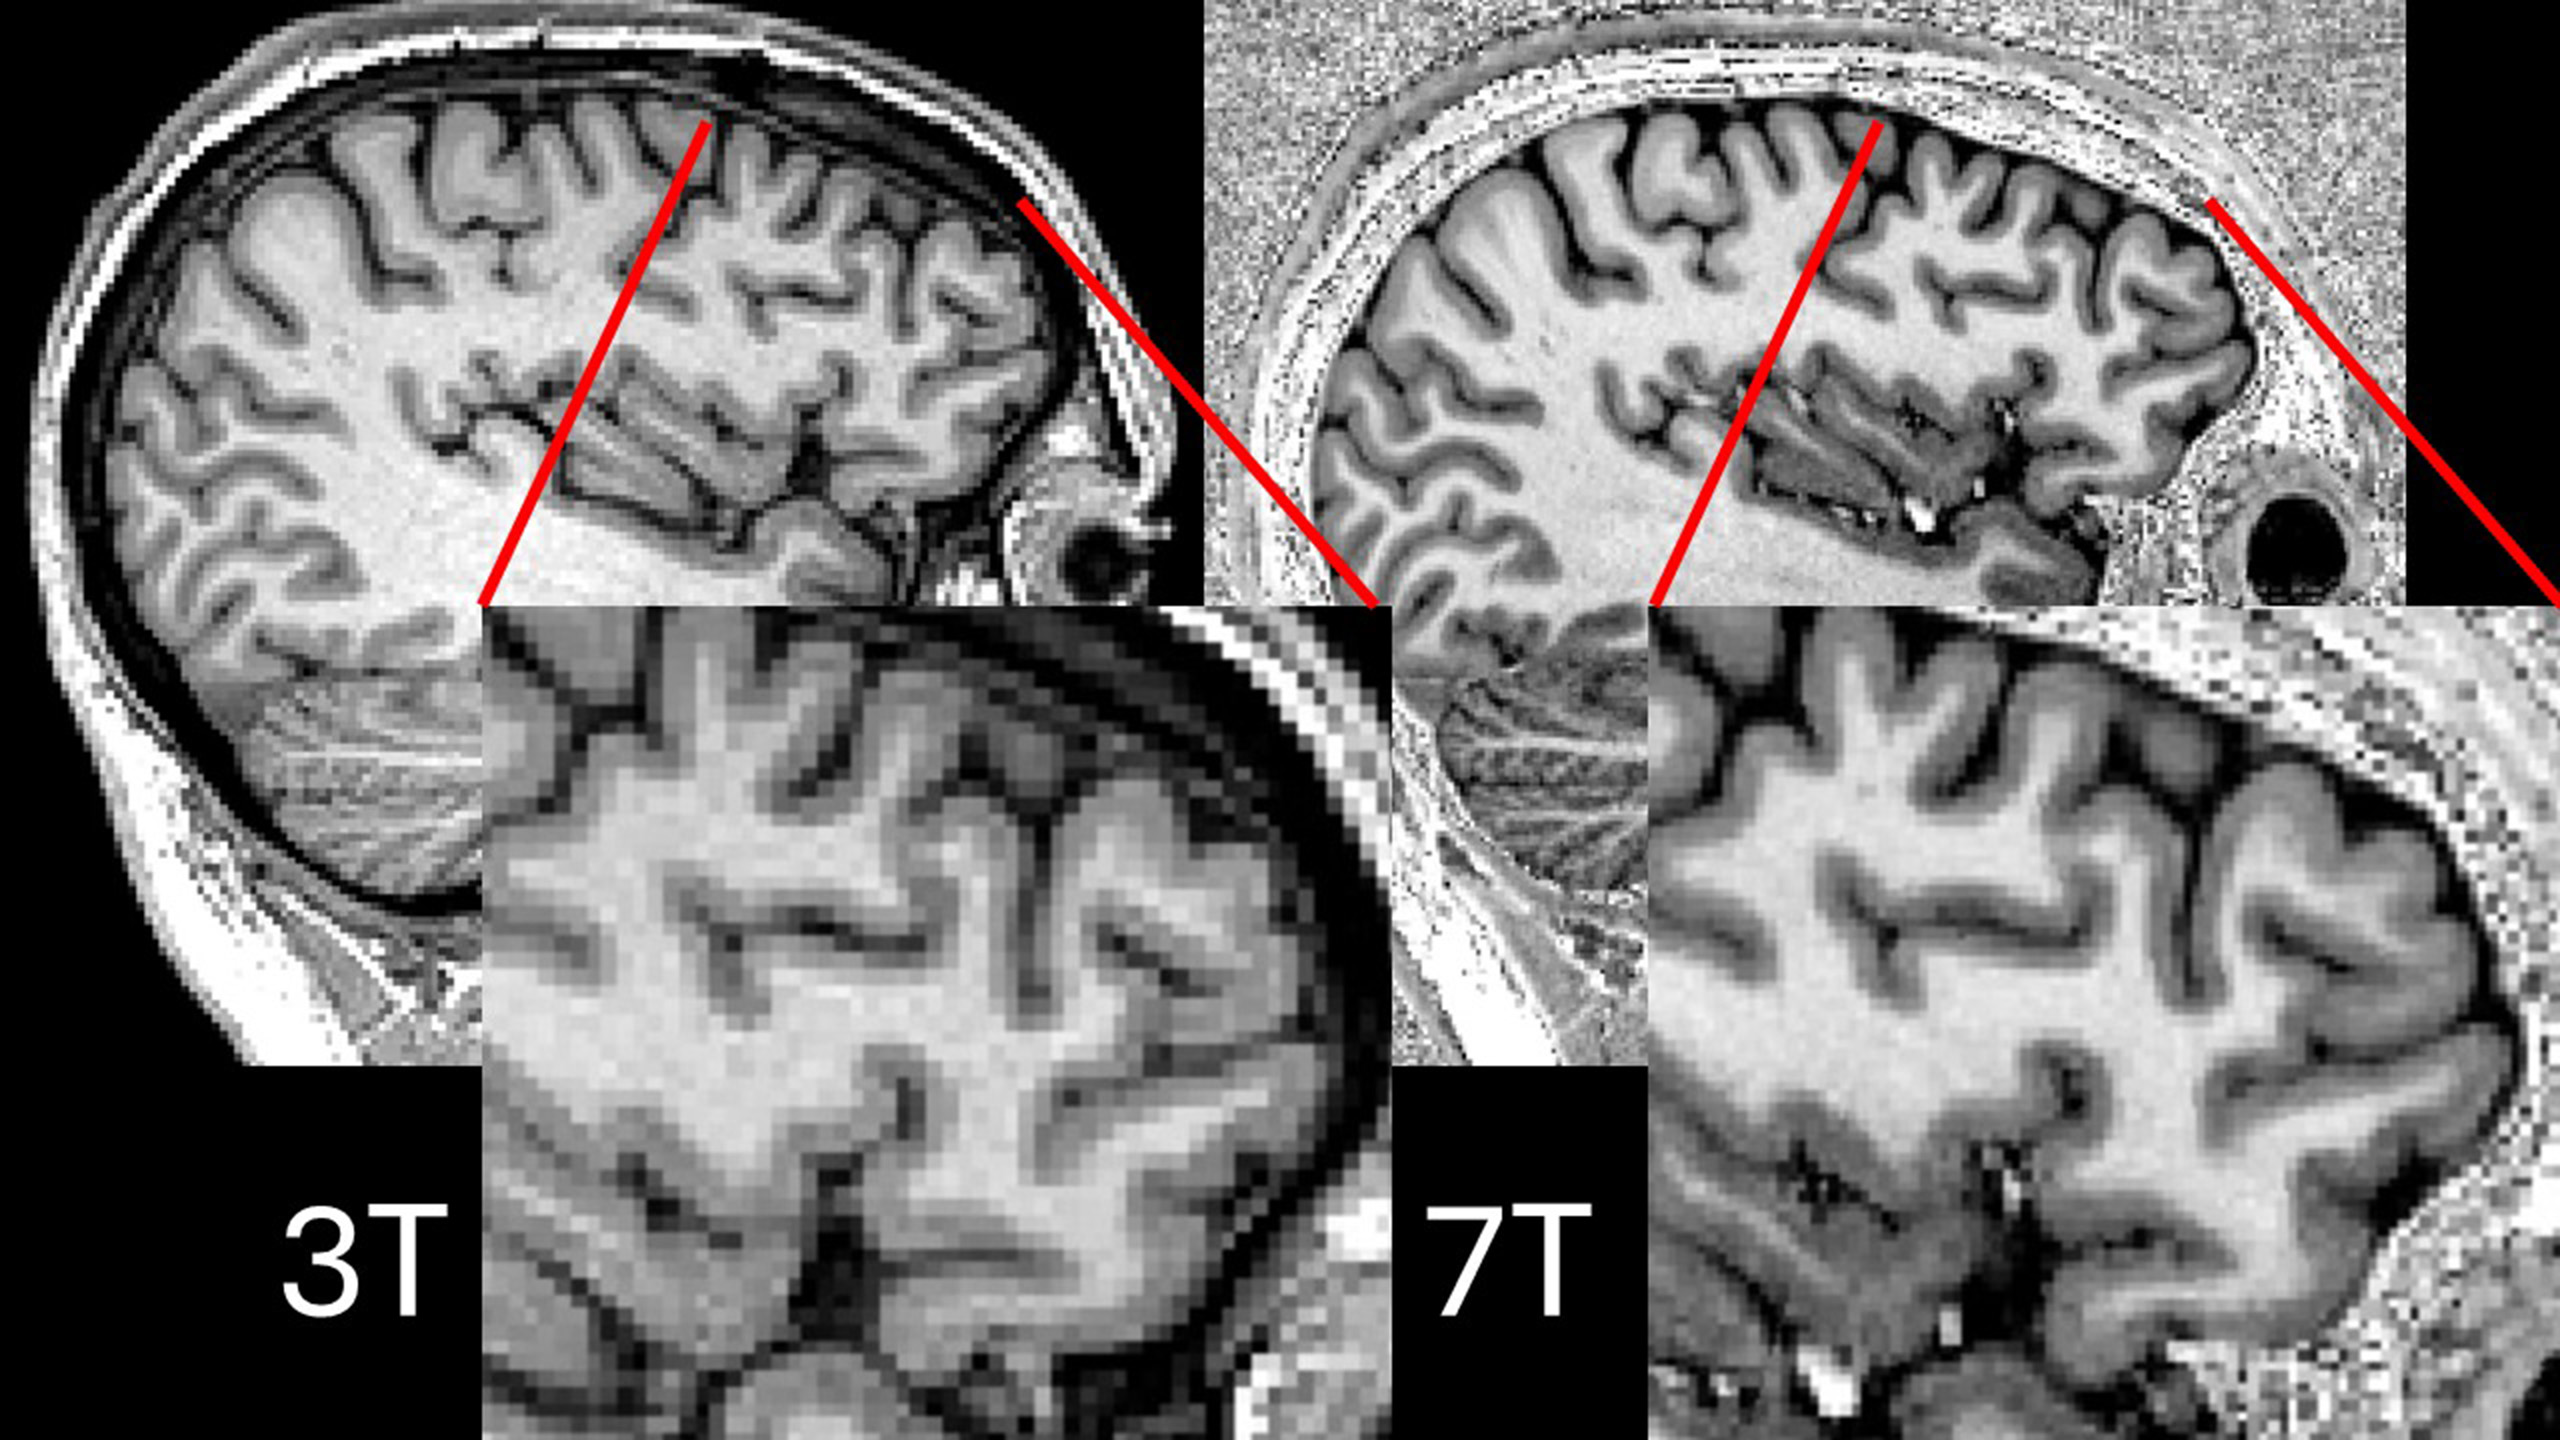

"Detailed MRI brain scans are used to find out the causes of epilepsy and can show if any parts of the brain are shrunken," said corresponding author Prof. John Duncan, head of the Department of Clinical and Experimental Epilepsy at the Institute of Neurology, UCL, in a university statement.

To address the knowledge gap, Fiore and colleagues conducted a study that included 84 people with temporal lobe epilepsy and hippocampal sclerosis and 43 people without these conditions. Patients underwent high-resolution MRI scans to measure the size and shape of different parts of the brain, including the cerebral cortex (which is responsible for thinking, memory, attention, perception, awareness, and language) and specific areas within the hippocampus (which helps with learning, memory, and spatial navigation). Study participants then underwent tests taken from the Adult Memory and Information Processing Battery to assess their verbal memory and the investigators compared the test scores to the sizes of different brain areas as visualized on MRI.